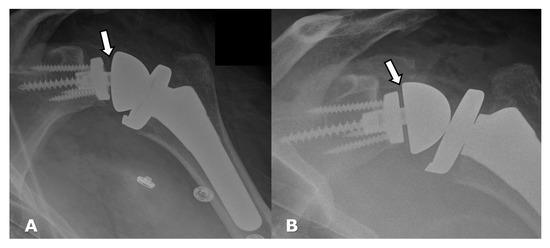

4.2.1. Loosening and Hardware Dissociation

5.1.1. Humeral Head Resurfacing/Stemless Hemiarthroplasty (HHRA)

5.1.2. Hemiarthroplasty (HA)

5.1.3. Anatomic Total Shoulder Arthroplasty (ATSA)